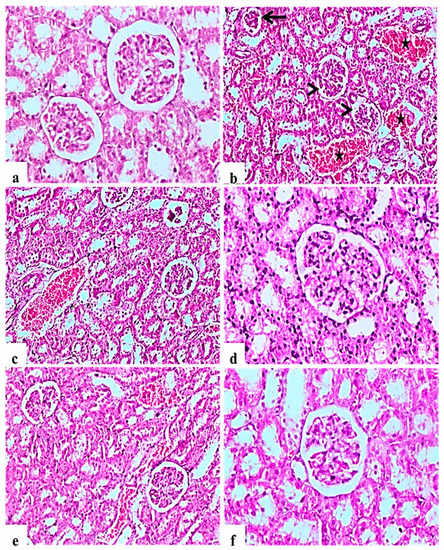

2.9.2. Kidney